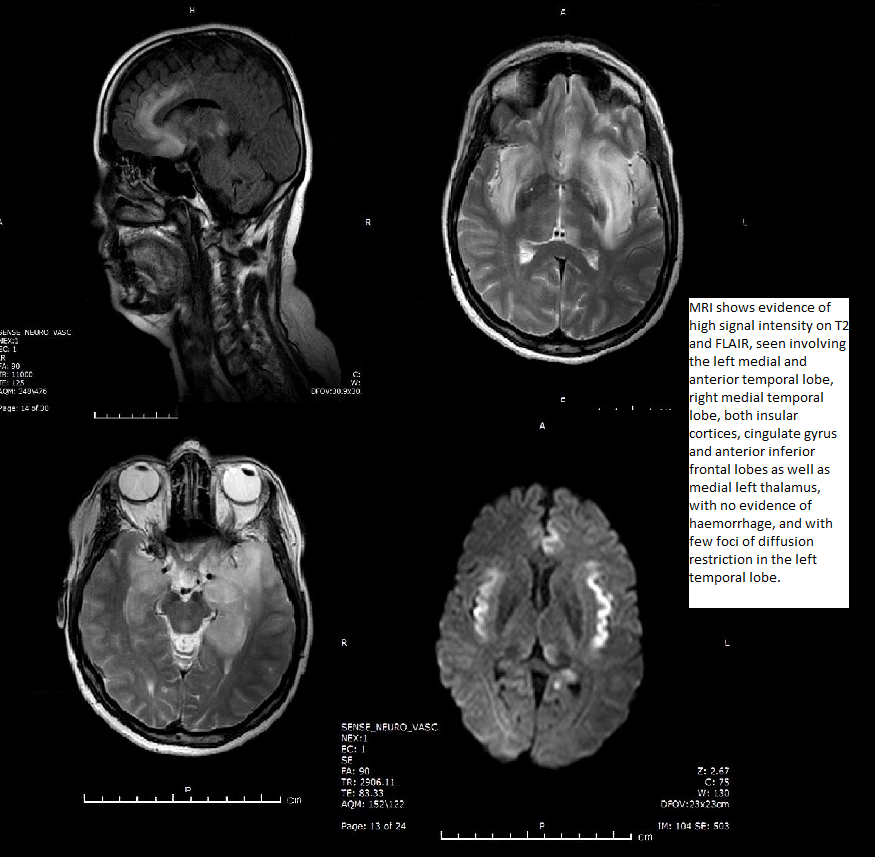

Imaging features of limbic encephalitis?

It is a paraneoplastic

syndrome associated with a primary malignancy, typically

lung or breast cancer. Imaging findings may be indistinguishable from herpes encephalitis with unilateral or bilateral regions

of signal abnormality with a predilection for limbic system; however, hemorrhage does not occur.

Clinically, the onset of symptoms is usually more insidious (weeks to months)

rather than acute. Treatment of the primary malignancy may result in stabilization or improvement of symptoms.